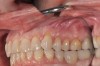

(26.) Guided-surgery template with inspection window.

Figure 26